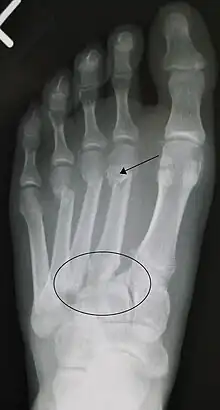

An X-ray of a Lisfranc injury

Lisfranc fracture (marked by the oval). This case also has fractures of the distal second (marked by the arrow), third, and fourth metatarsal bones.

In a high energy injury to the midfoot, such as a fall from a height or a motor vehicle accident, the diagnosis of a Lisfranc injury should, in theory at least, pose less of a challenge. There will be deformity of the midfoot and X-ray abnormalities should be obvious. Further, the nature of the injury will create heightened clinical suspicion and there may even be disruption of the overlying skin and compromise of the blood supply. Typical X-ray findings would include a gap between the base of the first and second toes.[8] The diagnosis becomes more challenging in the case of low energy incidents, such as might occur with a twisting injury on the racquetball court, or when an American Football lineman is forced back upon a foot that is already in a fully plantar flexed position. Then, there may only be complaint of inability to bear weight and some mild swelling of the forefoot or midfoot. Bruising of the arch has been described as diagnostic in these circumstances but may well be absent.[9] Typically, conventional radiography of the foot is utilized with standard non-weight bearing views, supplemented by weight bearing views which may demonstrate widening of the interval between the first and second toes, if the initial views fail to show abnormality. Unfortunately, radiographs in such circumstances have a sensitivity of 50% when non-weight bearing and 85% when weight bearing, meaning that they will appear normal in 15% of cases where a Lisfranc injury actually exists.[10] In the case of apparently normal x-rays, if clinical suspicion remains, advanced imaging such as magnetic resonance imaging (MRI) or computed tomography (CT scan) is a logical next step.[11]